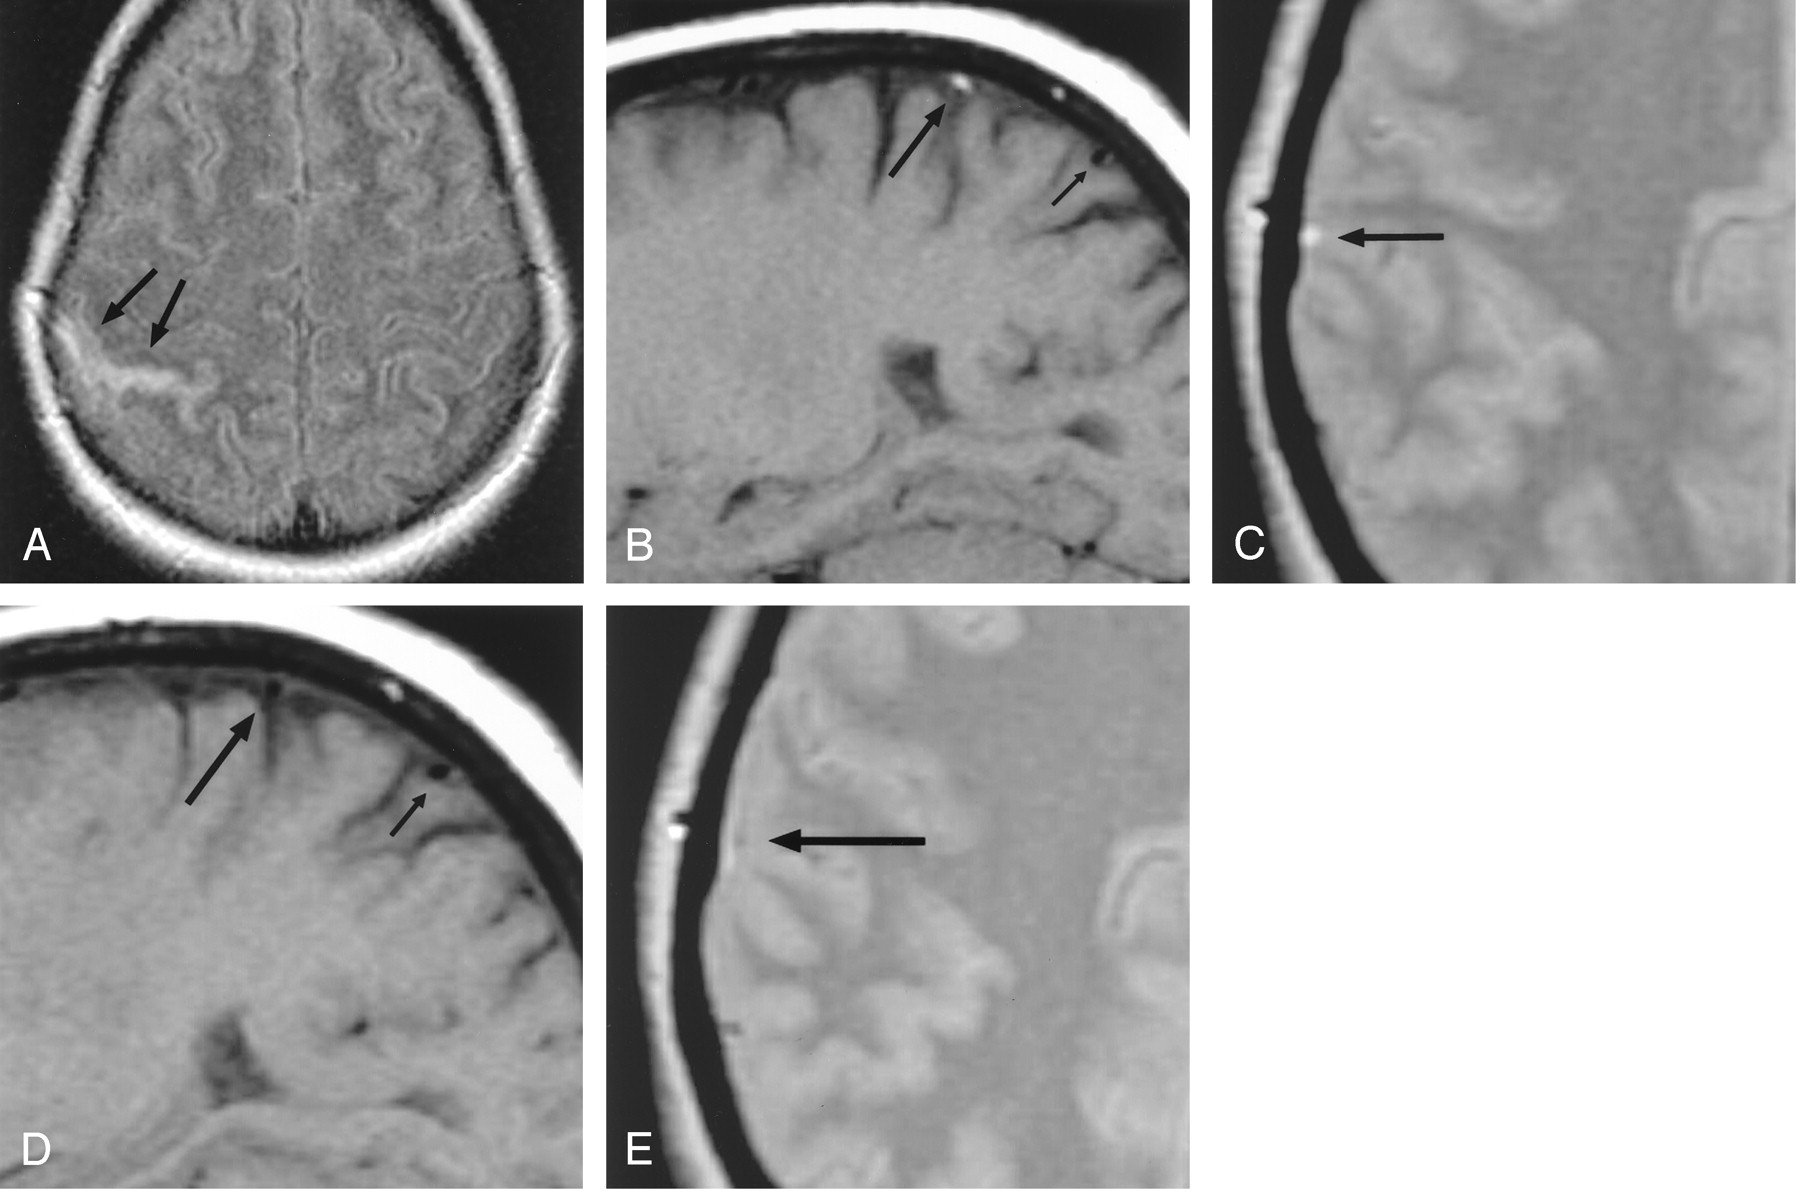

Patient 1, a 29-year-old woman with headaches, seizures, and cortical venous thrombosis.

A, Axial FLAIR (10,002/158/2200) [TR/TE/TI] MR image shows focal sulcal hyperintensity at the right frontoparietal convexity (arrows).

B, Right parasagittal T1-weighted (500/14) MR image shows tubular hyperintense thrombus (arrows) in a right convexity cortical vein, probably the vein of Trolard.

C, Right parasagittal T1-weighted (500/14) MR image, obtained approximately 3 months after the FLAIR image in panel A, shows resolution of the hyperintense thrombus (arrows).

D and E, Source data from MR venograms obtained at presentation (D) and approximately 3 months later (E) show interval appearance of flow signal intensity (arrows) in the previously occluded cortical vein.

Heparin and warfarin anticoagulation were initiated. She was also maintained on dilantin for seizure prophylaxis. A comprehensive hypercoagulability workup was unrevealing. The patient improved and continued to take warfarin as an outpatient.

Follow-up MR imaging was obtained approximately 3 months after the patient’s initial presentation. This examination showed interval resolution of the clot in the cortical vein (Fig 1C). In addition, partial recanalization of the thrombosed cortical vein was noted on MR venography (Figs 1D and E).